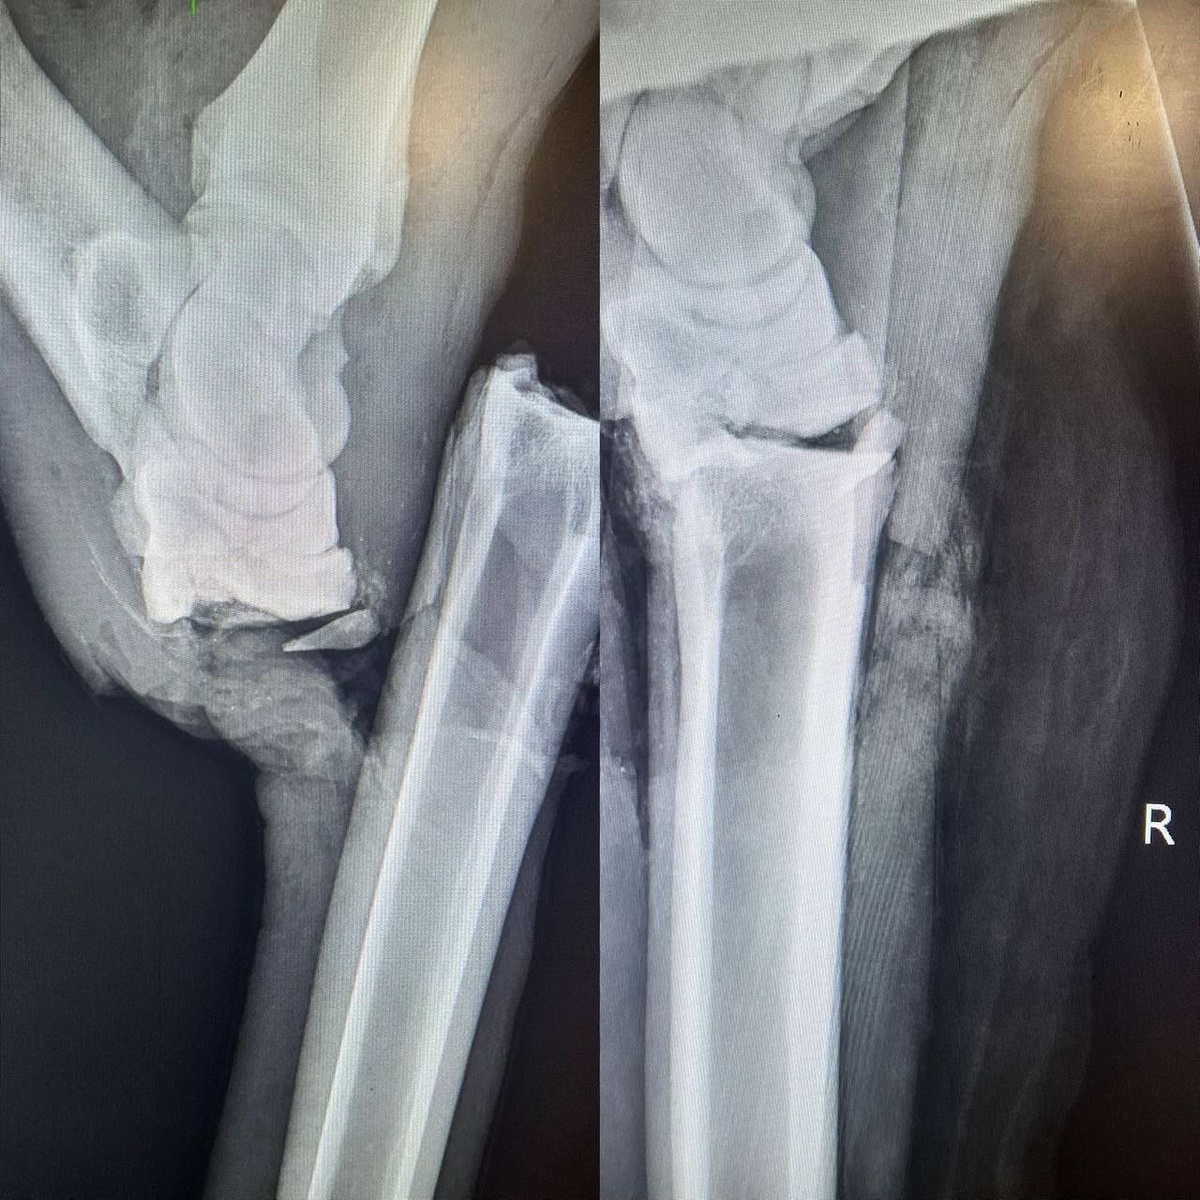

Врачи осмотрели его еще раз и решили везти в специальную ветклинику в Дмитрове. После долгого лежания на обочине у него развилось воспаление и возможны также повреждения внутренних органов.

Ножки уже загипсовали и готовят к операции. Если все пройдет успешно, то лося отвезут на реабилитацию в Лосиный остров.

Фото: Прокуратура МО